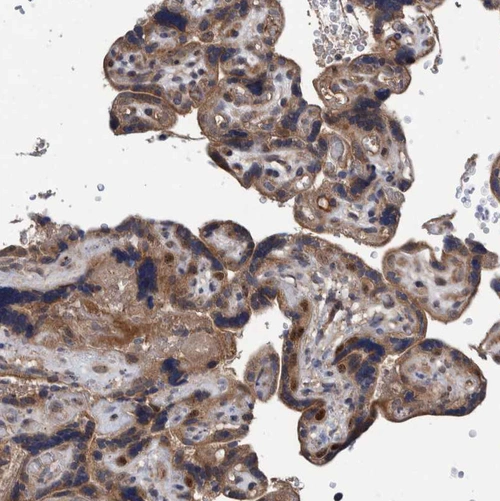

Immunohistochemical staining of human Liver shows strong cytoplasmic positivity in hepatocytes.